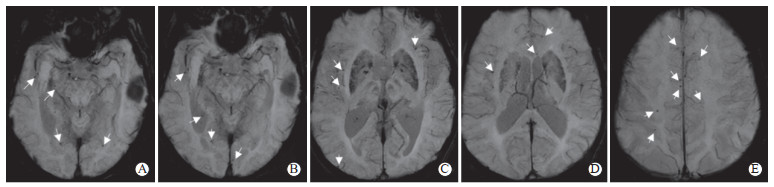

2022年9月25日加用甲泼尼龙500 mg/d连续5 d冲击治疗,序贯减停药物。2022年10月12日复查头颅MRI(图 1a~1h)提示:右侧颞叶、海马旁及边缘叶异常信号影较前缓解,右耳中耳道内可见T2WI高信号(图 4),请耳鼻喉科医师会诊,考虑右耳分泌性中耳炎,不排除原发病灶或前驱感染病灶可能。患者住院期间合并肺部感染,根据药敏试验结果给予足量、足疗程抗生素治疗后,肺部感染得到有效缓解。2022年10月14日,患者精神状态恢复,无言语错乱,对答切题,无肢体抽搐;近时记忆力下降,伴短时记忆障碍,患者为小学文化程度,简易智力状态检查量表得分22分,定向力及语言能力尚可,准予出院。出院后继续抗癫痫治疗,随访至今病情未复发。

图  4   患者治疗后头颅MRI检查

2022年10月12日,治疗后头颅MRI检查:A、B、C为T2WI序列,白色箭头所指可见右耳中耳道内异常高信号影.MRI:磁共振成像.

HSE患者常以发热、头痛为首发症状,随后可出现精神行为异常、局灶性神经功能缺损等表现。病情严重者可进一步发展为意识障碍、癫痫发作,甚至脑水肿[1-3]。上呼吸道感染前驱症状和额颞叶功能障碍可作为HSE的相对特异性症状[4]。本例患者病程中伴有胡言乱语、癫痫发作及认知功能障碍等额颞叶受累表现,头颅MRI检查提示双侧额颞叶不对称病灶。另外,本例患者在治疗后复查头颅MRI见右耳中耳道内T2WI高信号,耳鼻喉科检查可见右耳中耳腔少量积液及气泡,考虑右耳分泌性中耳炎,不排除原发病灶或前驱感染病灶可能。